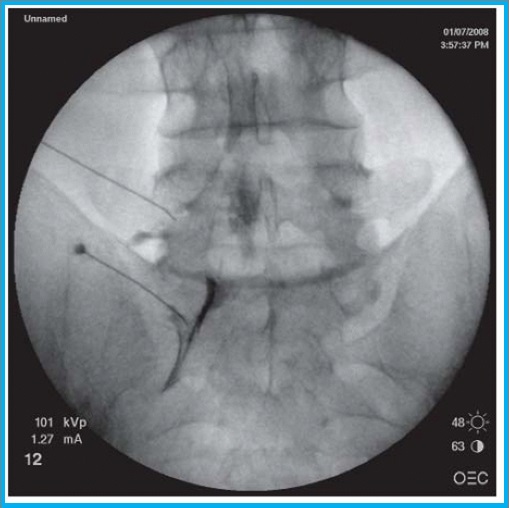

Η διατρηματική επισκληρίδιος έγχυση αποτελεί μια πιο εξειδικευμένη ιατρική πράξη, η οποία εφαρμόζεται κάτω από ακτινοσκοπικό έλεγχο και με χρήση σκιαγραφικής ουσίας για την απεικόνιση του νεύρου, όπου μικρή ποσότητα τοπικού αναισθητικού και κορτιζόνης εγχέεται απευθείας στο νευρικό τρήμα που αποτελεί το σημείο εξόδου του νεύρου από την σπονδυλική στήλη.